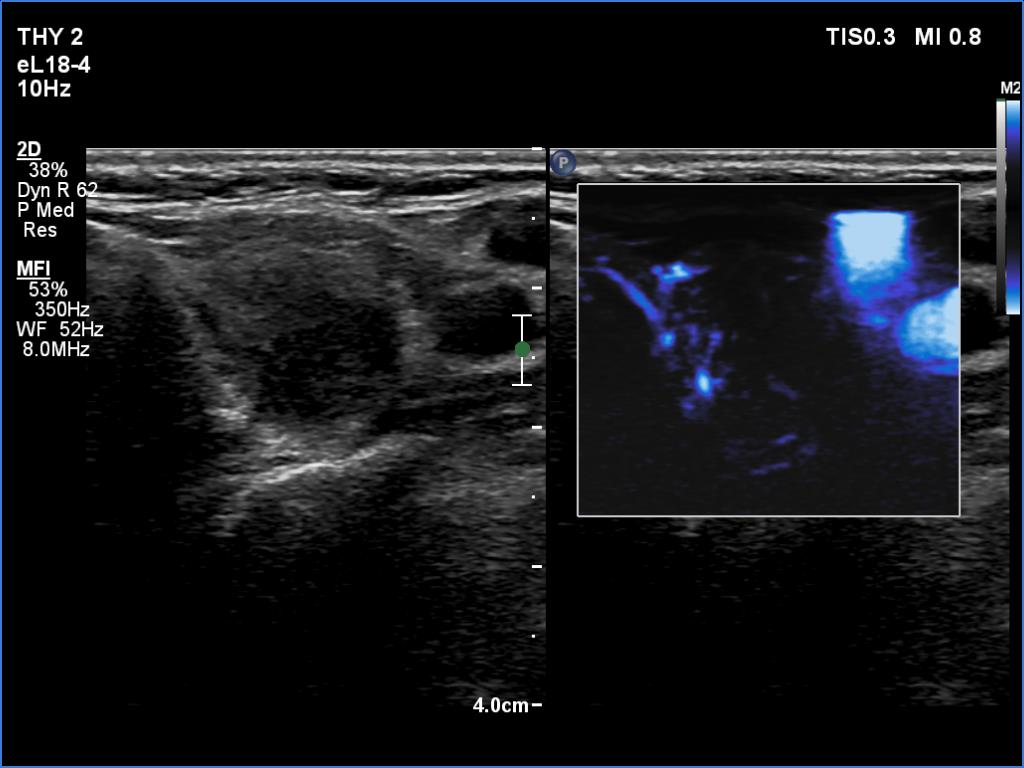

Right lobe, longitudinal scan

Left lobe, transverse scan, microflow imaging. The lesion has no vessels.